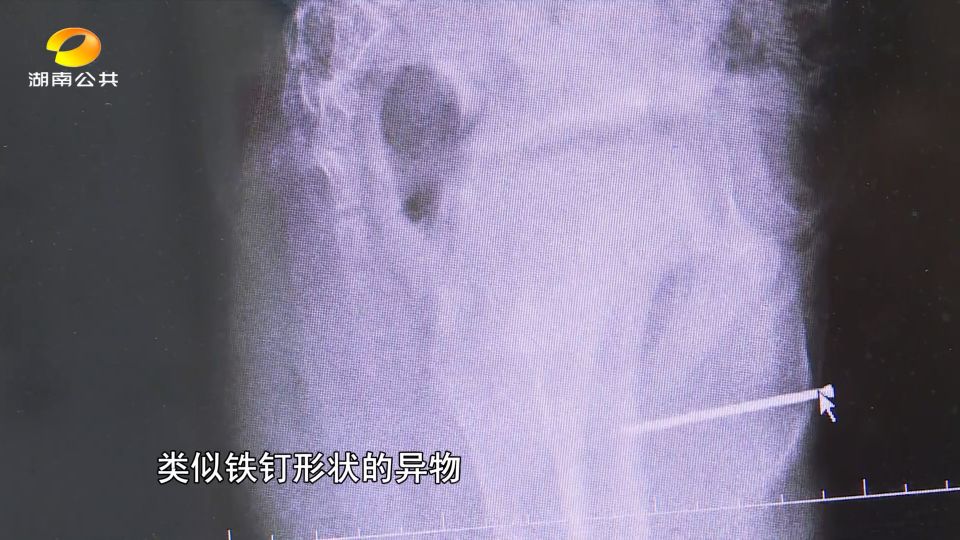

省儿童医院泌尿外科主治医师刘李表示:从这个片子上面可以看到,尿道位置有一根长约5厘米的类似铁钉钢钉的异物,差一点点就插到直肠里面去了。

医生检查时,患儿尿道外口仍见少量脓性分泌物,各项检查结果出来之后,也让异物慢慢显出原形,小明的尿道异物疑似铁钉。

而小明也不愿透露事发的经过,2月13日上午,医生通过手术成功将这颗长约4.7cm,明显锈迹斑斑的铁钉取出。